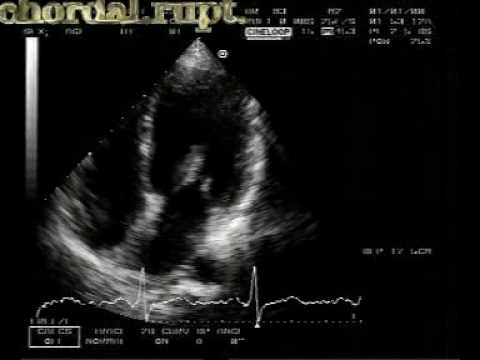

Chordal Rupture (2/2) • Video • MEDtube.net

medtube.net

medtube.net

rupture chordal echocardiogram video

Double Valve Replacement For Acute Spontaneous Left Chordal Rupture

cardiothoracicsurgery.biomedcentral.com

cardiothoracicsurgery.biomedcentral.com

ruptured chordae mitral echocardiogram rupture transesophageal anterior chordal aortic leaflet incompetence chronic spontaneous acute